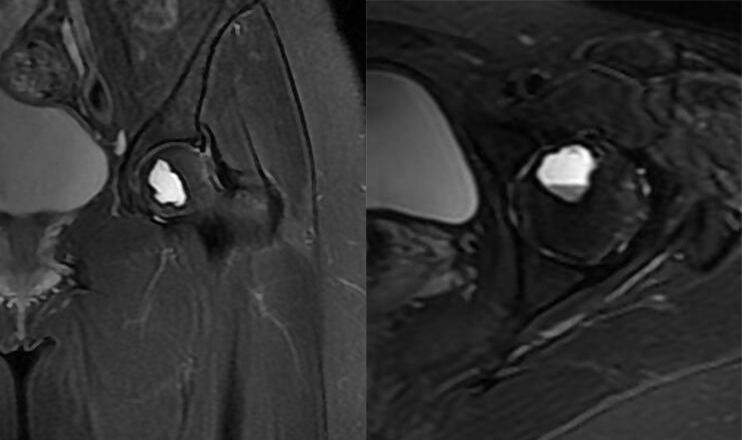

瘤软骨

瘤软骨为肿瘤细胞产生的软骨基质,多来源于软骨类肿瘤,或内有化生瘤软骨成分的其他肿瘤如成软骨型骨肉瘤。瘤软骨为软组织密度,未钙化时,主要通过 MRI 检查显示。由于瘤软骨多由富含水分及粘多糖的透明软骨构成,故 T1WI 呈偏低信号,T2WI 或 PDWI 呈明显高信号,被低信号的纤维间隔分开呈分叶状(图 24、图 25a-b),增强扫描多呈不均匀分隔状强化(图 25c),主要是纤维间隔强化,瘤软骨强化不明显之故。

图 24.瘤软骨:内生软骨瘤

图 25.瘤软骨:内生软骨瘤